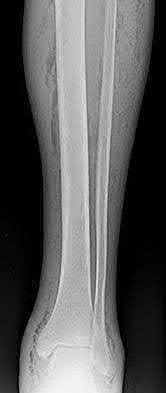

Question 19:

A 28-year-old male sustains a closed comminuted tibial shaft fracture. Two hours post-injury, he develops severe leg pain unyielding to narcotics. His blood pressure is 120/80 mmHg. Intracompartmental pressure monitoring is performed. Based on current guidelines, which measurement dictates an emergent 4-compartment fasciotomy?

Options:

- Absolute compartment pressure > 20 mmHg

- Absolute compartment pressure > 25 mmHg

- Delta pressure (Diastolic BP - Compartment Pressure) < 30 mmHg

- Delta pressure (Systolic BP - Compartment Pressure) < 30 mmHg

- Delta pressure (Mean Arterial Pressure - Compartment Pressure) < 40 mmHg

Correct Answer: Delta pressure (Diastolic BP - Compartment Pressure) < 30 mmHg

Explanation:

Acute compartment syndrome is classically defined by tissue hypoperfusion. The absolute compartment pressure is less reliable than the differential pressure (Delta P). A Delta P (Diastolic Blood Pressure minus Compartment Pressure) of less than 30 mmHg is an absolute indication for emergency fasciotomy, as capillary perfusion gradient is lost when tissue pressure approaches the diastolic pressure.